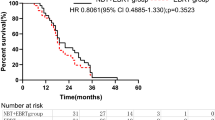

The esophageal toxicity prediction for the four DEs was listed in Table 3. Compared with the SD-IMRT plan, the predicted grade ≥ 2 AET values using the Kwint model in the SIB-IMRT group were 2.9%, 3.1%, 2.2% and 1.6% higher on average for ESOwhole, ESOinfield, ESOinfield-tumor and ESOwhole-tumor, respectively. Grade ≥ 2 AET predicted using the Wijsman predicting model were 14.6%, 13.2%, 7.2% and 3.4% higher on average. Additonally, the SIB-IMRT plan was also 4.3%, 7.2%, 4.2% and 1.2% higher on average for grade ≥ 3 AET. The predicted LET were increased by 0.15%, 0.39%, 1.2 × 10−2% and 1.5 × 10−3% for the four DEs. Compared with ESOwhole-tumor and ESOinfield-tumor, the increase was higher with the ESOwhole and ESOinfield definition.

Whether different DEs influence the evaluation of the esophageal toxicity prediction for EC patients administered SIB-IMRT vs. SD-IMRT remains unknown. To address this issue, we employed four DEs to distinguish the changes on esophageal toxicity prediction between the SIB-IMRT and SD-IMRT dosing regimens using radiobiological models. We found that different DEs influence the esophageal toxicity prediction by up to 11.2% (grade ≥ 2 AET predicted with the Wijsman model). To the best of our knowledge, this study is the first to investigate the influence of different DEs on the esophageal toxicity prediction for EC patients received SIB-IMRT vs. SD-IMRT.

Although two dosimetric studies demonstrated an improved benefit of SIB-IMRT compared with the SD-IMRT strategy12, 17, no further information on esophageal toxicity was provided in the two studies. Until recently, the DEs are not consistent for EC patients. Whether the portion of esophagus outside the treatment field should be included in the toxicity prediction is unclear. Caglar et al. suggested that the in-field esophagus was a new predictor for esophagitis in NSCLC patients10. However, other studies used the entire esophagus as the predictor6, 7, 18. Interestingly, we found that two DEs (ESOwhole and ESOinfield) resulted in a similar trend of increase for esophageal toxicity prediction in the SIB-IMRT plans (Table 3), indicating that both of them are comparable for esophageal toxicity evaluation. However, we also found that the increase in esophageal toxicity using ESOwhole and ESOinfield was higher than that of the ESOwhole-tumor and ESOinfield-tumor, particularly when the Wijsman model was used (Table 3). Therefore, more attention should be paid on a consensus on the DEs during the radiation therapy treatment for EC patients.